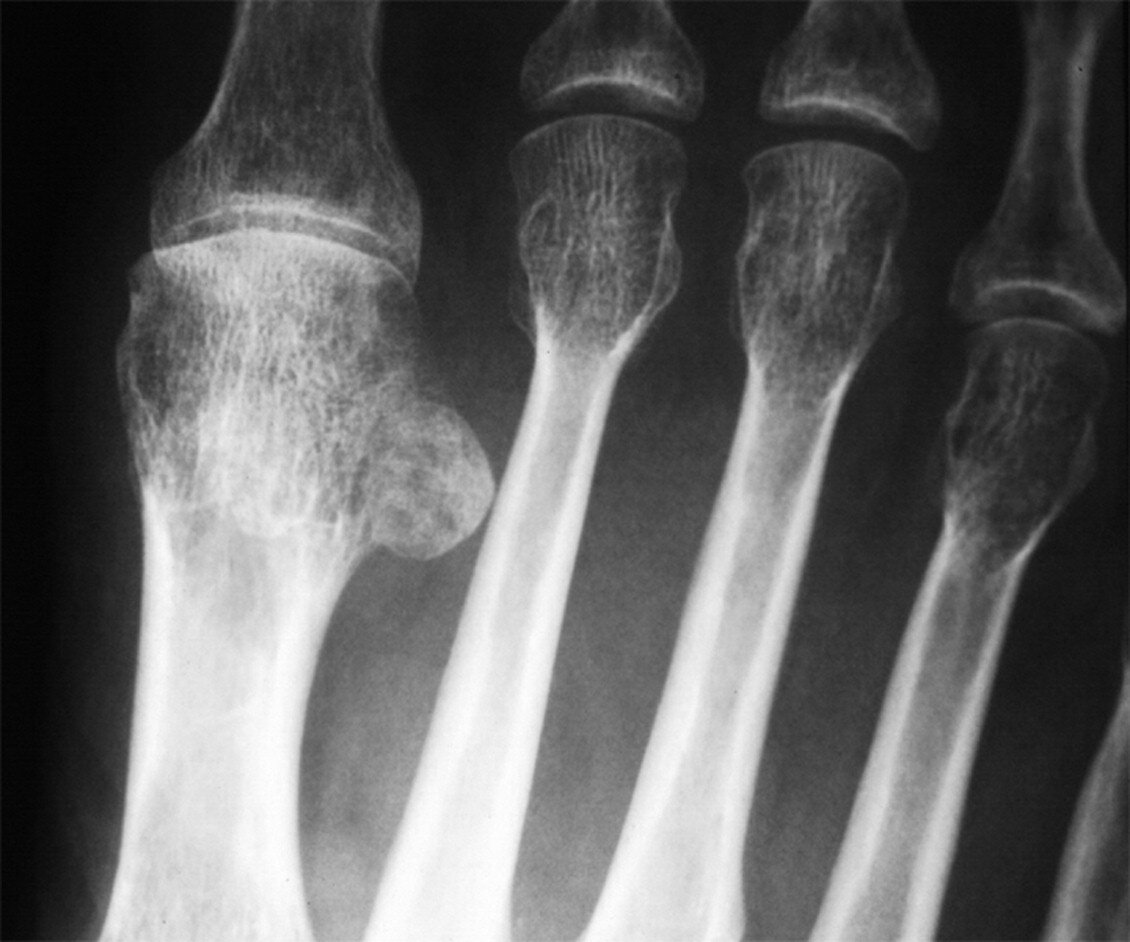

Il piede solitamente è gonfio ed il dolore e continuo, di tipo urente e aggravato dal carico. Concomitano iperalgesia e rigidità articolare; la cute appare secca iperidrosica ed eritematosa. Radiograficamente è presente osteoporosi loco-regionale (è interessato solo il piede) su base neurovascolare.